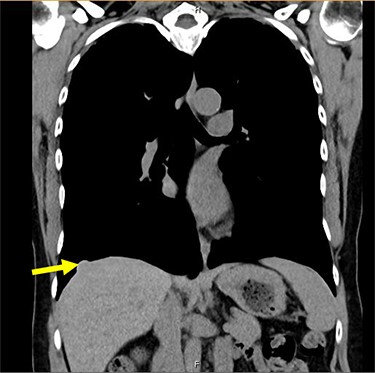

A 54-year-old female without prior thoraco-abdominal trauma presented to the office with two right lower lobe lung nodules. The nodules were initially noted incidentally on a computerized tomography (CT) scan in August 2009 and measured 1.5 cm × 2.8 cm and 0.9 cm × 1.3 cm (Figs 1 and 2). A follow-up CT scan and positron emission tomography (PET) performed in 2010 demonstrated that the nodules were stable in size. The patient was lost to follow-up until March 2019 when she had a CT scan for concern for pneumonia. On these images, the lung nodules had increased in size to 2.8 cm × 4.1 cm and 1.1 cm × 1.4 cm. The patient was otherwise asymptomatic. A PET scan was obtained which showed hypermetabolic nodules with maximum SUV of 3.29 and 1.4, for the larger and smaller nodule, respectively (Figs 3 and 4). Radiographic appearance as well as the growth pattern was consistent with low-grade malignancy suspicious for carcinoid tumor. CT-guided biopsy was not feasible because of location of the tumor.

Liver herniation corresponding to the location of smaller lung nodule seen on CT scan.